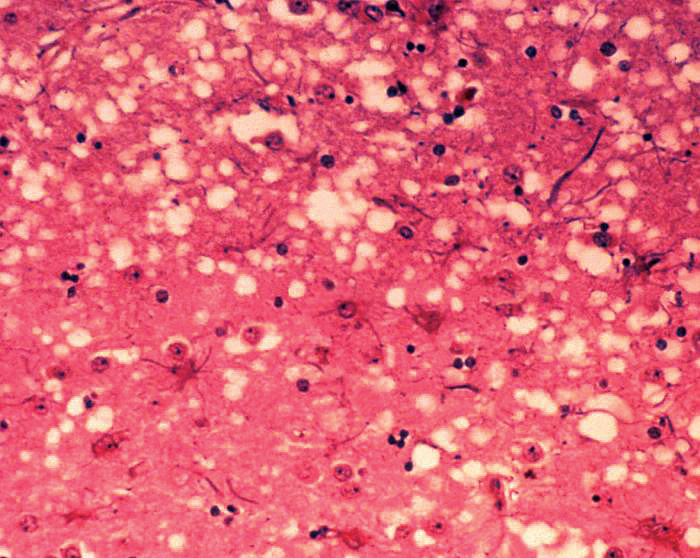

غير أن أشهر أوبئة القرن العشرين كان وباء “الأنفلونزا الإسبانية”، الذي تزامن انتشاره مع نهاية الحرب العالمية الأولى سنة 1918م وسمي آنذاك بـ “الجريب”. فقد قضى هذا الوباء على أكثر من ثلاثين مليوناً من البشر خلال ستة أشهر فقط، في حين أن ضحايا الحرب على مدى أربع سنوات كانوا تسعة ملايين فقط! وقد تفشّى هذا المرض عالمياً حتى إنه أعطى اسمه لاحقاً في الثقافة الشعبية لمرض الأنفلونزا ككل، وذلك لتشابه عوارض الوباءين.